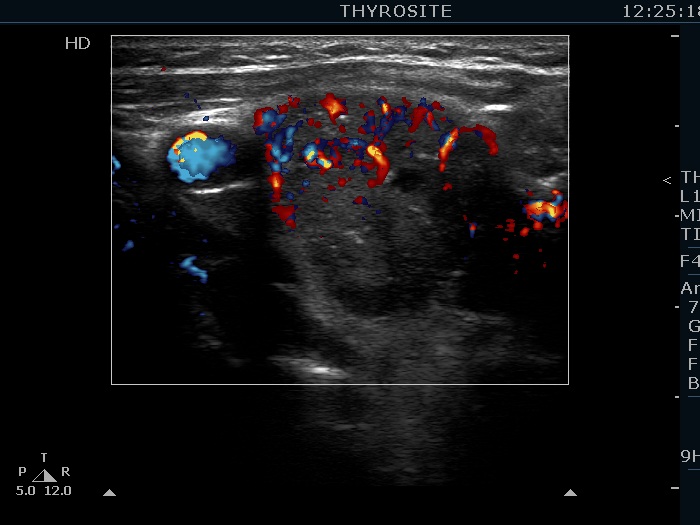

Intranodular hyperechogenic figures - case 876 (ultrasonographic picture 4)

Right lobe, horizontal view, color Doppler mode. The nodule has intranodular blood flow.